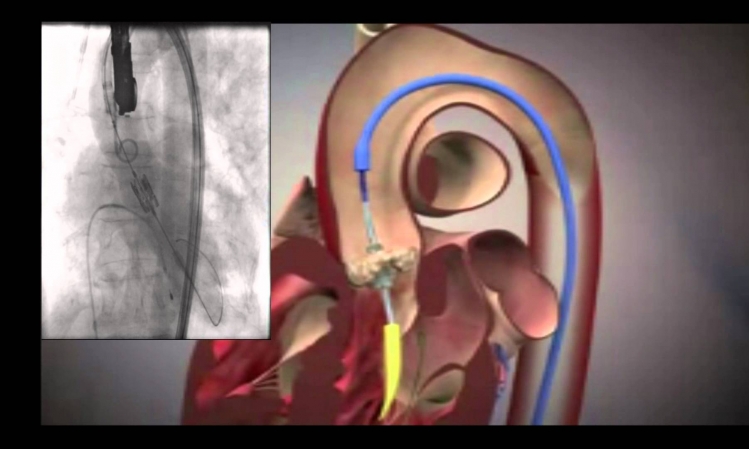

وأجريت العملية الأولى من نوعها بواسطة تِقنيَّات جديدة عَالية الدِّقة، حيث تَمَّ إصلاح الصمّام التاجي ، عَبْر إدْخال أُنبوب طِبِّي من الفَخْذِ، خِلال الوَريد، حتى الأُذَيْن الأيْمَن ومن ثم اختراق الحاجز ما بين الأُذنيْن للوصول الى البُطَيْن الأيْسَر في القلب، حتى زِراعة كابِس في الصَّمام المُصاب .

وتتمثل وظيفة الصمّام التاجي في منع عودة الدم من البُطيْن الأيسر الى الأُذَيْن الأيْسر ، لكن عِدِّة أمراض في عضلة القلب والصمّام نفسه تُؤدي الى عدم إغلاق الصمِّام بشكل مُحْكَم ، ومن عوارض هذه الحالة على المريض ضيق التنفُّس والضعف الحركي والتعب وتراكم السَّوَائل في الرّئتين وفي القسم السُّفلي من الجسم ِ.